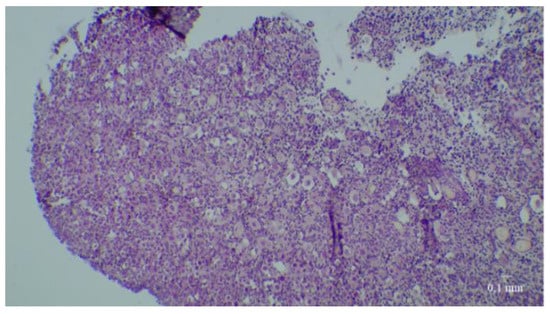

Figure 2.

Fresh fetal ovarian tissue before culture. Slices colored before culture with hematoxylin-eosin-safran at low and high magnification.

At D0, nearly 72% of fresh tissue follicles were primordial follicles; there were also a few intermediate and primary follicles but no secondary follicles (Figure 2). It is important to note that no tertiary follicles were seen at any time in any culture.